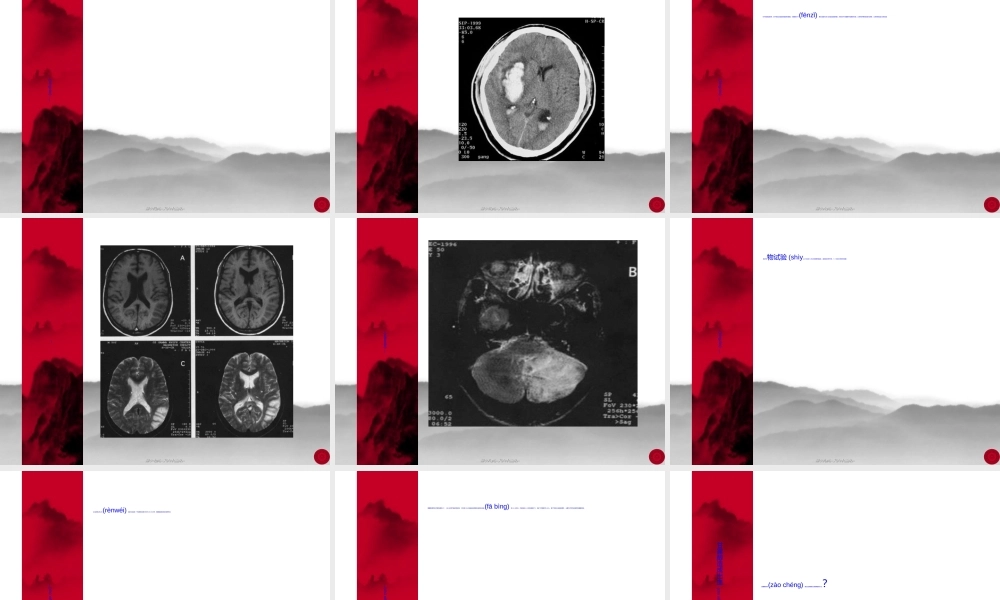

甘露醇规范甘露醇规范应用及脑出应用及脑出血的诊疗血的诊疗(zhěnliáo)(zhěnliáo)流程流程周口市中心医院神经内科程乾第一页,共六十二页。第一页,共六十二页。甘露醇的药理机制(jīzhì)和特点20%的甘露醇是六碳多元醇,其分子量为163是尿素(niàosù)的三倍,PH值为5-7。为高渗透压性脱水剂,无毒性,作用稳定。第二页,共六十二页。第二页,共六十二页。甘露醇的药理机制(jīzhì)和特点甘露醇静脉注入机体后,血浆渗透压迅速提高,其主要分布在细胞外液,仅有一小部分(约为总量的3%)在肝脏内转化为糖元,绝大部分(97%)经肾小球迅速滤过,造成高渗透压,阻碍肾小管对水的再吸收;同时它能扩张肾小动脉,增加(zēngjiā)肾血流量,从而产生利尿作用。第三页,共六十二页。第三页,共六十二页。甘露醇的药理(yàolǐ)机制和特点甘露醇对机体的血糖干扰不大,对患有糖尿病的患者仍可应用。由于血浆渗透压迅速提高形成了血-脑脊液间的渗透压差,水分从脑组织及脑脊液中移向血循环,由肾脏排出。使细胞内外(nèiwài)液量减少,从而达到减轻脑水肿、降低颅内压目的。第四页,共六十二页。第四页,共六十二页。甘露醇的药理(yàolǐ)机制和特点甘露醇也可能具有减少脑脊液分泌(fēnmì)和增加其再吸收,最终使脑脊液容量减少而降低颅内压。第五页,共六十二页。第五页,共六十二页。甘露醇的药理(yàolǐ)机制和特点甘露醇的降颅压作用,不是单纯的利尿,而是主要在于(zàiyú)造成血液渗透压增高,使脑组织的水分吸入血液,从而减轻脑水肿、降低颅内压。第六页,共六十二页。第六页,共六十二页。甘露醇的药理(yàolǐ)机制和特点一般在静脉注射后20分钟内起作用,2-3小时降压作用达到高峰(gāofēng),可维持4-6小时。常用剂量为0.25-0.5克/kg.次成人一次用量。第七页,共六十二页。第七页,共六十二页。甘露醇的副作用临床实践证明,甘露醇除了能引起低钾等电解质紊乱,也可诱发或加重(jiāzhòng)心衰、血尿、肾功不全、肾功衰竭等。甘露醇可使正常血脑屏障开放。第八页,共六十二页。第八页,共六十二页。脑出血时甘露醇作用(zuòyòng)机制及时机选择⑴随着CT和MRI的广泛应用,发现血肿进行性扩大者比例较高。血肿的扩大与血压增高的程度、凝血功能、出血部位以及血肿形态(xíngtài)等因素有关。第九页,共六十二页。第九页,共六十二页。脑出血时甘露醇作用机制(jīzhì)及时机选择⑵从血管破裂出血开始直至与血肿内压力平衡,最后(z...